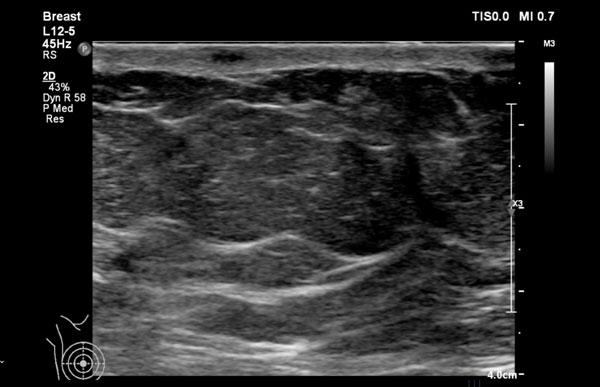

Trong cùng một tuyến vú có thể tồn tại các vùng có nhiều mô mỡ xen kẽ với các vùng chủ yếu là mô xơ tuyến, như có thể thấy trên video.

Khi quan sát đường bờ của mô tuyến (mũi tên), có thể hình dung rằng khi sờ nắn sẽ cảm thấy gồ ghề và đôi khi tạo cảm giác như có một khối u khi mô tuyến rất phát triển.